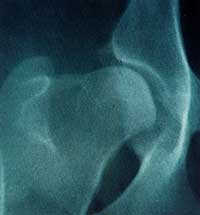

| HOW DO I GET MY DOG'S HIPS X-RAYED? An

owner should make an appointment with their veterinary surgeon

for hip radiography to be carried out under the scheme. This

may require admission to the veterinary practice for a short

period or a day. Sedation or general anaesthesia will be required

since the manual restraint of animals during radiography is

only permitted under exceptional circumstances. Additionally,

the radiograph must be of the highest photographic quality and

the projection of all the required structures must be as dictated

by the rules of the scheme (copies of which are available from

theBVA).The advice of the practice staff should be followed

regarding any period of 'nilby mouth', the time of the appointment

and the need in every case to presentat the time of the procedure

the Kennel Club registration and, if appropriate, transfer certificates.

It is a requirement of the scheme that the registration number

is indelibly printed on to the radiograph. It will be necessary

for the owner of the dog or his agent to sign the scoring sheet

there by signifying the identity of the animal in question and

associated details, giving permission forthe results to be published

and to be subjected to genetical and statistical research.The

minimum age of the dog at the time of the radiography is 12

months; there is no upper age limit. Dogs may not be scored

under the scheme more than once.The cost of the procedure will

be a composite of the veterinary surgeon's feefor taking the

radiograph and the fee forwarded with the film to the BVA. The

latter covers the fees paid to the scrutineers appointed under

the scheme, are imbursement of costs incurred by the Kennel

Club and an administration charge made by the BVA. |